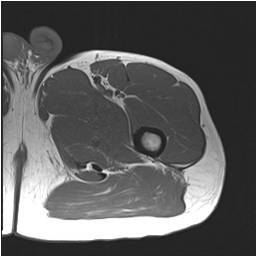

Gallery of Unlabled Radiographs from Lecture (Dr. French) - 2020

Click a thumbnail to enter the gallery display. Click the file name link at the bottom left of the gallery display to view the image at high resolution.

Labeled Plates from Lecture (Dr. French) - 2020

RadiologyLowerLimbThoraxQuestionPoolLabeled_01_2020.pdf

Click right side of plate to step forward or left side of plate to step backward.